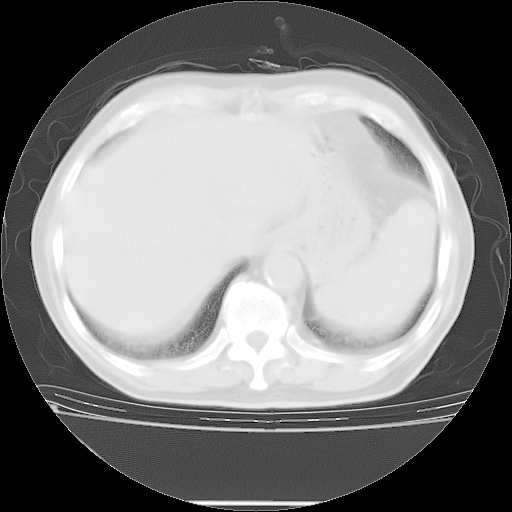

今天复查肺部CT,发现双肺广泛磨玻璃样改变。所以我把3月19日和5月9日相隔50天的肺部CT上传。请大家会诊。

5月9日肺部CT(在4月27日齐鲁医院肺部CT描述部分肺组织磨玻璃样改变,12天后肺组织广泛磨玻璃样改变)

2009年5月9日肺部CT

大致读了系列胸部CT:纵隔窗无明显异常,肺窗:从4、27至今:主要是双肺中下野外带可见毛玻璃样改变,目前处于急性肺泡炎阶段,至于原因考虑1、结替组织或胶原血管性疾病所致?2、恶性疾病如恶组在肺部所致的表现或细支气管肺泡癌?3、药物或其它原因如肺蛋白沉着症所致肺泡炎目前不太可能?总之,明天就去请我院的呼吸科、感染科、血液科和临免专家会诊哈。